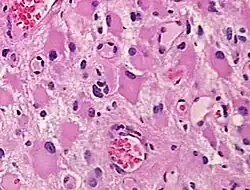

A gemistocyte (/dʒɛˈmɪstəsaɪt/ jem-ISS-tə-syte; from Greek γέμιζω (gemizo) 'to fill up') is a swollen, reactive astrocyte.

Gemistocytes are glial cells that are characterized by billowing, eosinophilic cytoplasm and a peripherally positioned, flattened nucleus. Gemistocytes most often appear during acute injury; and eventually, shrink in size.[1] They are usually present in anoxic-ischemic brains, which occurs when there is a complete lack of blood flow to the brain. Anoxic-ischemic brains usually occur in patients who have had cardiac arrest and prolonged attempt at cardiopulmonary resuscitation.[2]